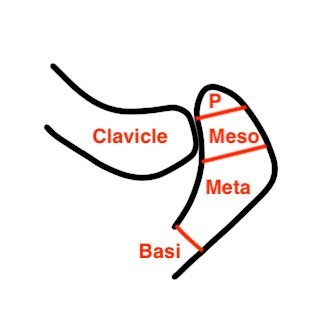

Anatomy

4 ossification centers present in acromion

- pre-acromion

- meso-acromion

- meta-acromion

- basia-cromion

The basiacromion fuses to spine of scapula by 12

Pre / Meso / Meta appear by 18

- unite by age 22 - 25

- if un-united by age 25 = Os Acromiale